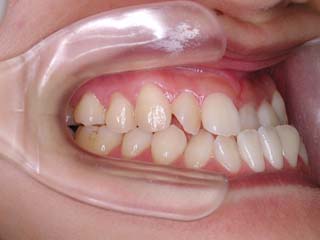

主訴:上の歯が出ている

診断名:顎関節症、下顎左右5欠損を伴う骨格性上顎前突

年齢:35歳

使用した主な装置名:TPB、マルチブラケット装置

抜歯/非抜歯および抜歯部位:非抜歯

治療期間:動的処置2年、経過観察3年

費用の目安:保険適応 自己負担金として30~50万

リスク、副作用:外科手術によるリスク、マルチブラケット治療に伴う歯根吸収など偶発症が発生するリスクがある。

強い骨格性の上顎前突が見られます。しばしば、口腔内所見では骨格のズレを歯の補償的な傾斜などでカムフラージュさせているため、あまり大したことのないズレにしか見えない事があります。また、上顎前突の場合は、下顎が関節の位置で知らず知らずのうちに前方へ大きく偏位させて噛んでいる事が多いです。このような場合は、咬合器に装着してみて初めて、治療方針が見えてくるかもしれません。どのような不正咬合であれ、大きなズレに対しては、外科的に骨のズレを改善する治療が理にかなっています。前後のズレ、垂直のズレと条件が重なってきた場合、より外科矯正での改善が望ましいでしょう。

一般的な外科矯正治療の流れは、術前矯正・外科矯正・術後矯正・保定治療と移行します。術後矯正では、手術後に僅かに見られる後戻りに対する処置や、刻々と変化する額関節の環境に対応して調節を続けます。特に大きな問題が無ければ6か月程度で保定治療に移行します。